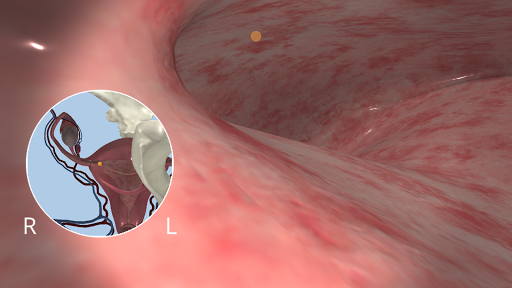

Anatomyou VR to edukacyjna aplikacja mobilna, która prezentuje w sposób wciągający ludzką anatomię.

Korzystając z wirtualnej rzeczywistości, będziesz w stanie poruszać się wzdłuż struktur anatomicznych, stając się częścią ludzkiej anatomii: układu rozrodczego układu krążenia, oddechowego, trawiennego, moczowego, łzowego i żeńskiego.

Anatomyou VR może być używany w dwóch różnych trybach: Virtual Reality i Fullscreen.

Mimo że zapewnia najlepszą jakość w trybie Virtual Reality, użytkownik może również korzystać z tej aplikacji mobilnej w trybie pełnoekranowym, bez potrzeby korzystania z gadżetu rzeczywistości wirtualnej.